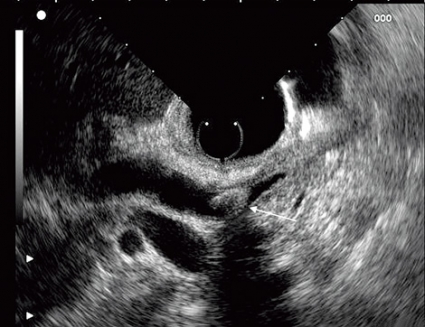

Det första instrumentet tillverkades 1980 och bestod av en enkel mekanisk ultraljudstransduktor kopplad till ett vanligt gastroskop. I dag finns två typer av elektroniska ekoendoskop: det radiella och det linjära. Det radiella instrumentet återger en ultraljudsbild i 360° som är vinkelrät mot instrumentet, medan det linjära instrumentet ger en bild som är parallell med instrumentets axel. Bara det linjära instrumentet möjliggör vägledning av en nål för finnålsaspiration, biopsi eller injektion genom att nålen kan följas i realtid vid införandet i vävnaderna (Figur 1).